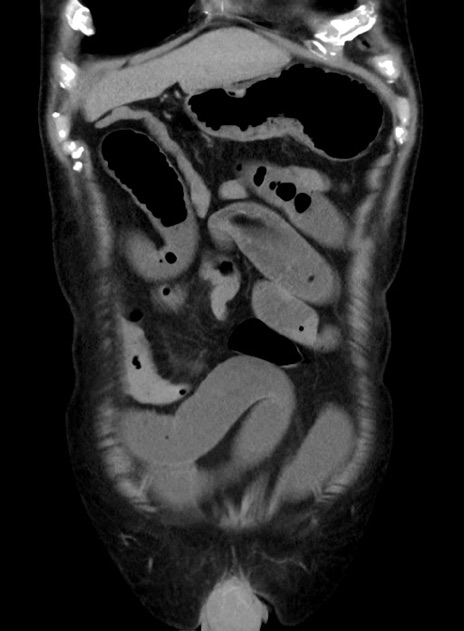

症例38(冠状断像)

【症例】70歳代 男性

【主訴】腹痛・嘔吐

【現病歴】昨晩より、嘔吐・腹痛あり。今朝になっても嘔吐あり。来院。

【既往歴】心臓バイパス手術、開腹胆摘、腸閉塞

【身体所見】BP 107/71mmHg、HR 116/min、腹部:平坦、軟、下腹部に軽度圧痛あり。反跳痛なし。

【データ】WBC 15100、CRP 0.32